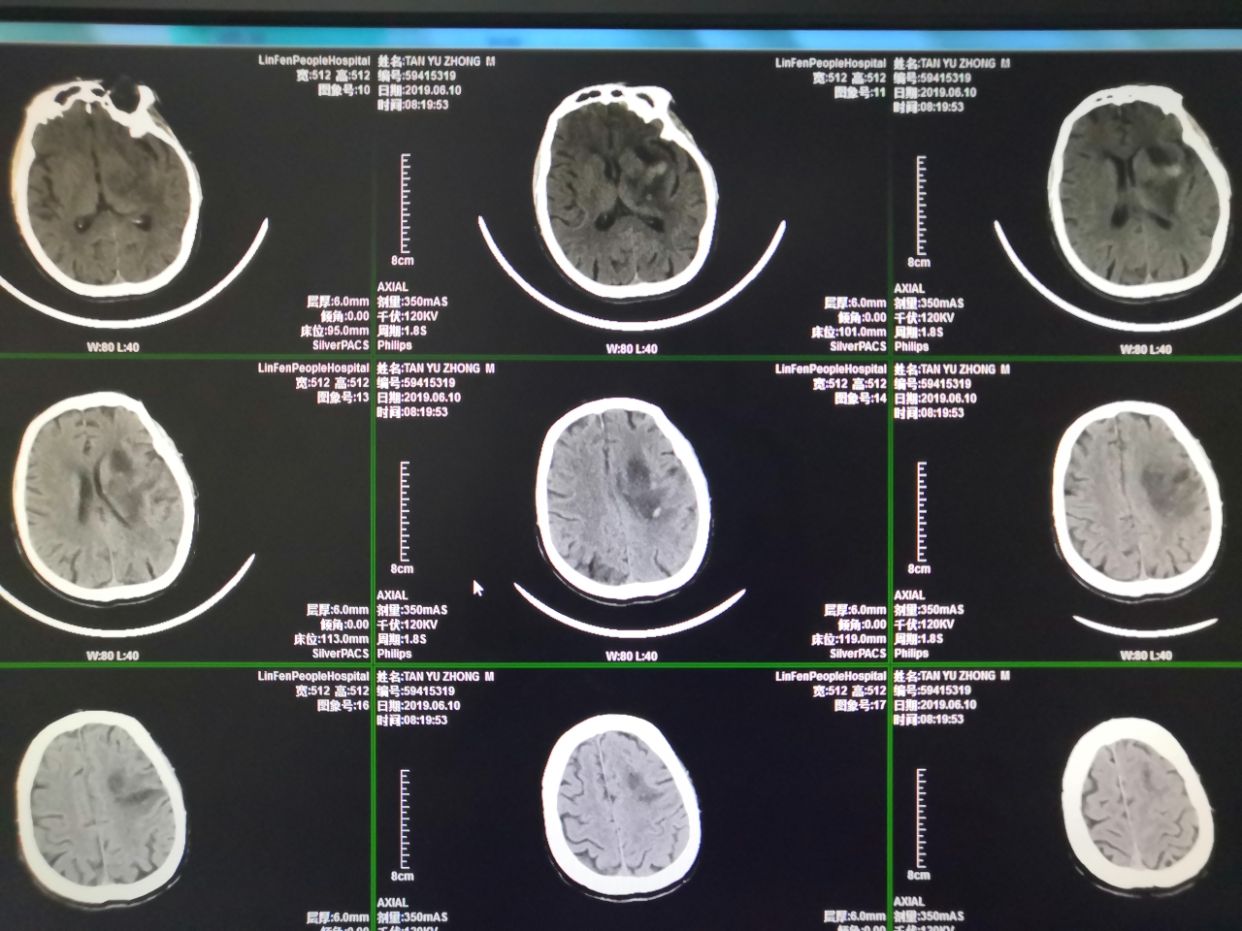

术后第一天,血肿清除率大于90%